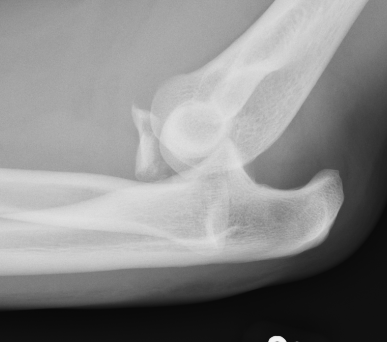

mason 1 CT Radial Head Fracture Type 3 radial head

rh orif Radial Head Replacement Lateral